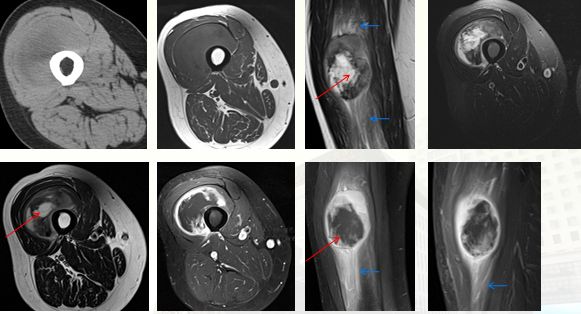

左肩三角肌内结节性筋膜炎

细胞型、肌肉。T2WI 示病灶呈不均匀高信号(白箭),中央可见条带状低信号纤维化(红箭);T1WI 示病灶呈等信号(白箭),中央可见条带状低信号纤维成分;增强扫描示病灶明显不均匀强化(箭),边界清晰,中央低信号强化不明显。

粘液型结节性筋膜炎

T1WI:左前壁皮下稍高信号结节灶,无包膜,边界模糊。T2WI:皮下混杂高信号结节灶,内见条带状低信号(红箭),邻近筋膜与病灶关系密切、增厚。增强扫描显示病灶周边及邻近筋膜明显强化,可见「筋膜尾征」(蓝箭),病灶中央强化不明显。